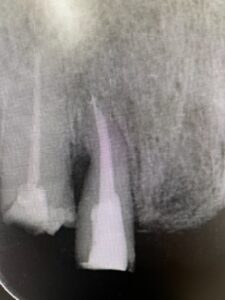

時折見かける根管内部への破折器具の残留です。やや左に見える白く光るものが破折ファイルです。これを肉眼で見て取り除くのは不可能です。

マイクロスコープを使用すると除去することが出来ます。